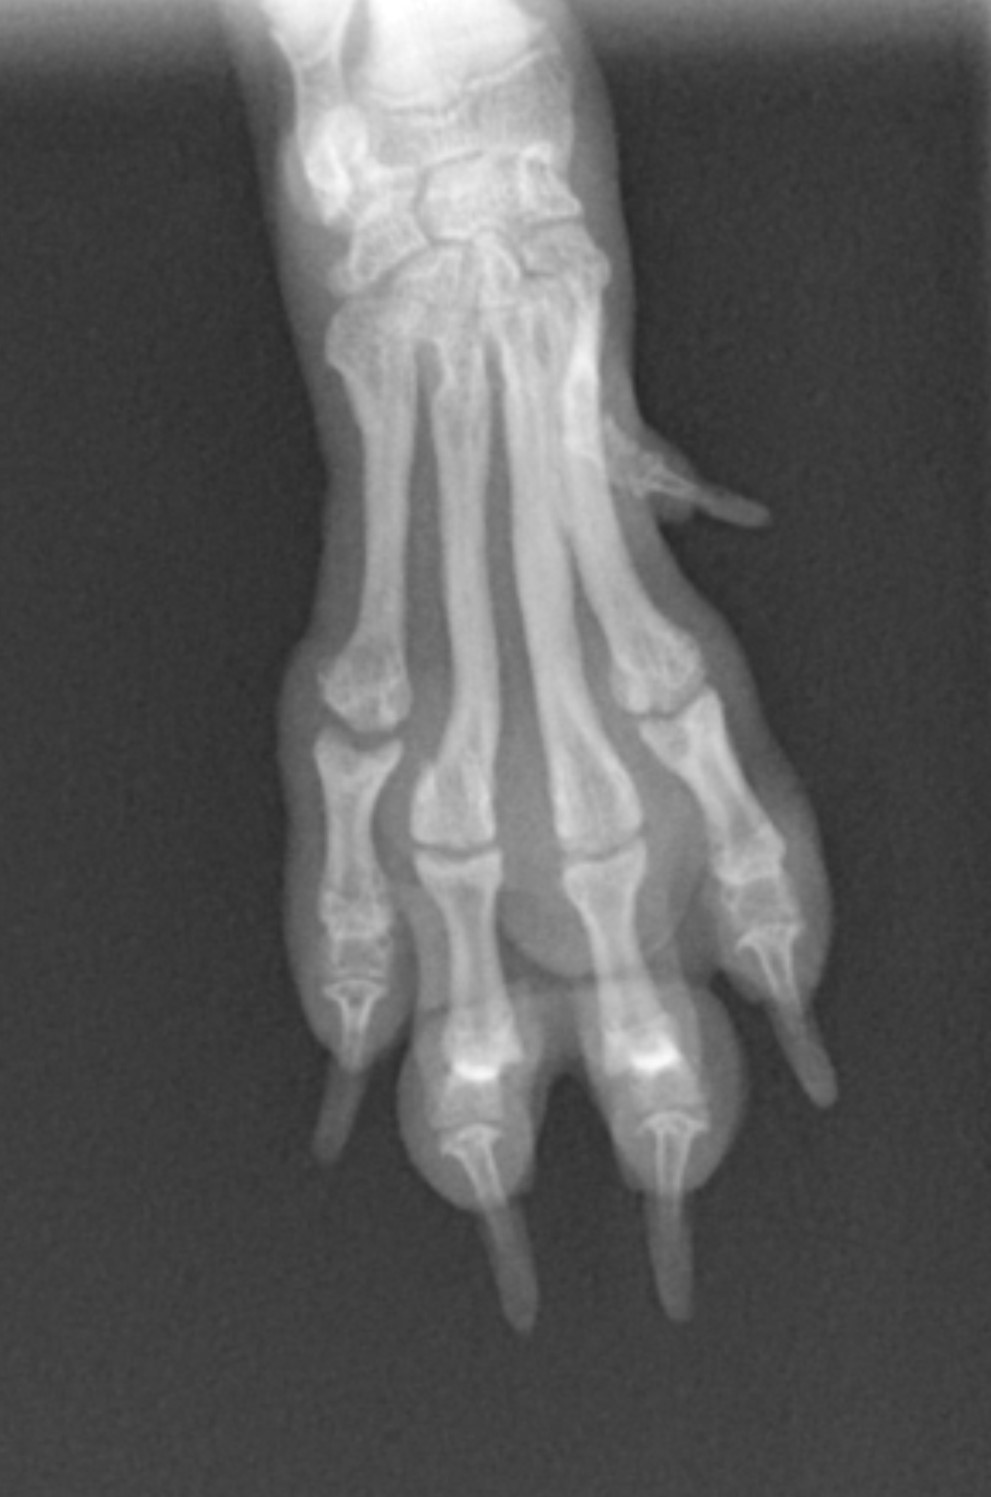

骨折した骨の幅は2.5mmほどでプレートを設置するには骨幅が狭すぎたため、ピンニング法を選

択しました。ピンは直径0.8mmを用意しました。 遠位より近位に向けて関節を貫通しないように

挿入し、のちに抜去する予定で遠位端は骨の外に出し、曲げています。この後数日から数週間おき

に細かくレントゲンを撮りながらずれていないか確認しながら経過を観察しました。